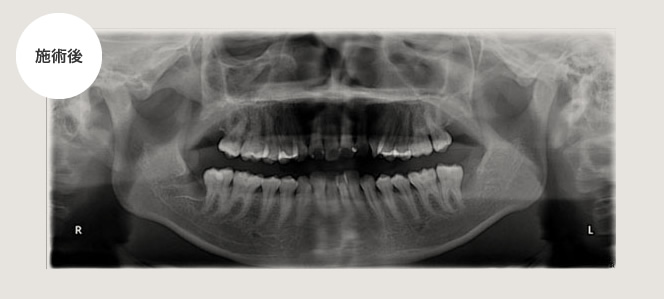

腫れが強い場合

左下が腫れて痛いという主訴で来院され、その日は抗生剤の投与及び消毒をして1週間後に腫れが減少してから抜きました。時間は約30分ぐらいで比較的術後の腫れもなかったです。

その後患者さんからこれぐらいの腫れと痛みならということで、3ヵ月後に右下の親知らずも抜いてくれということで、抜きました。

所要時間は約30分で術後の腫れも前回と同じくらいとのことでした。